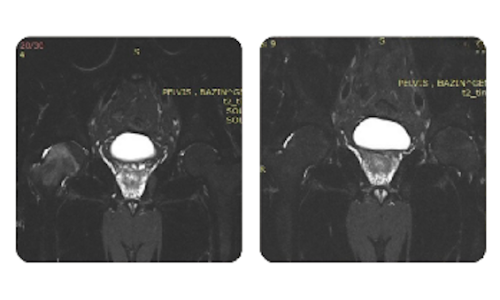

I progressi dei nostri pazienti, misurati prima e dopo la terapia iperbarica, riflettono l'efficacia e l'impatto positivo del trattamento. Scopri i risultati documentati della terapia iperbarica presso la clinica Hyperbarium Oradea, basati su valutazioni cliniche e dati oggettivi che evidenziano miglioramenti significativi in diverse condizioni.